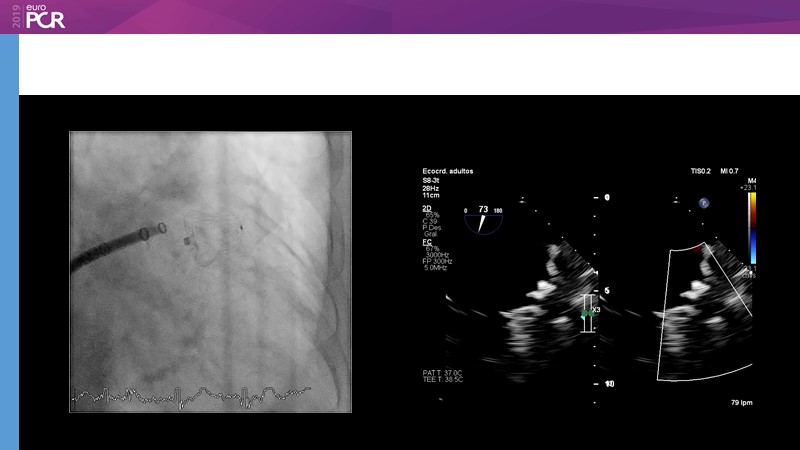

LAA closure

Left atrial appendage closure - A case-based discussion

Optimising procedural outcome and safety